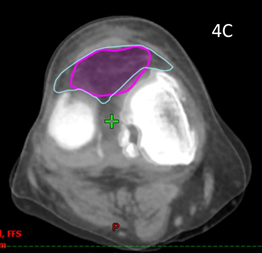

Patient 5 had treatment of a symptomatic left knee. The planning scan showed an effusion measuring 43.0cm3. Three months later the final CBCT of phase one showed a volume of 37.7cm3. A further three months later the final CBCT of phase two showed a volume of 33cm3, an overall decrease of 25%, even though he had increased activity by restarting playing soccer in that time. The reduction from planning CT to the final CBCT is shown in figure is shown in Figure 4. The effusion decreased in volume even though the dose was prescribed to bone. The reduction in the effusion associated with a reduction in symptoms and a better quality QoL points to this effect being more than just placebo as some have opined.

Figure 4 Decrease in size of knee effusion with two phases of 3 Gy in 6 fractions over three months.

Figure 4A Axial planning CT scan through the knee showing effusion coloured in light blue measuring 43.0cm3.

Figure 4B Axial planning CBCT scan taken during the last fraction of Phase 2 through the knee with effusion coloured in purple showing a volume of 33cm3.

Figure 4C Fusion of the above two scans showing significant shrinkage of 25% of the effusion from baseline to end of phase 2.